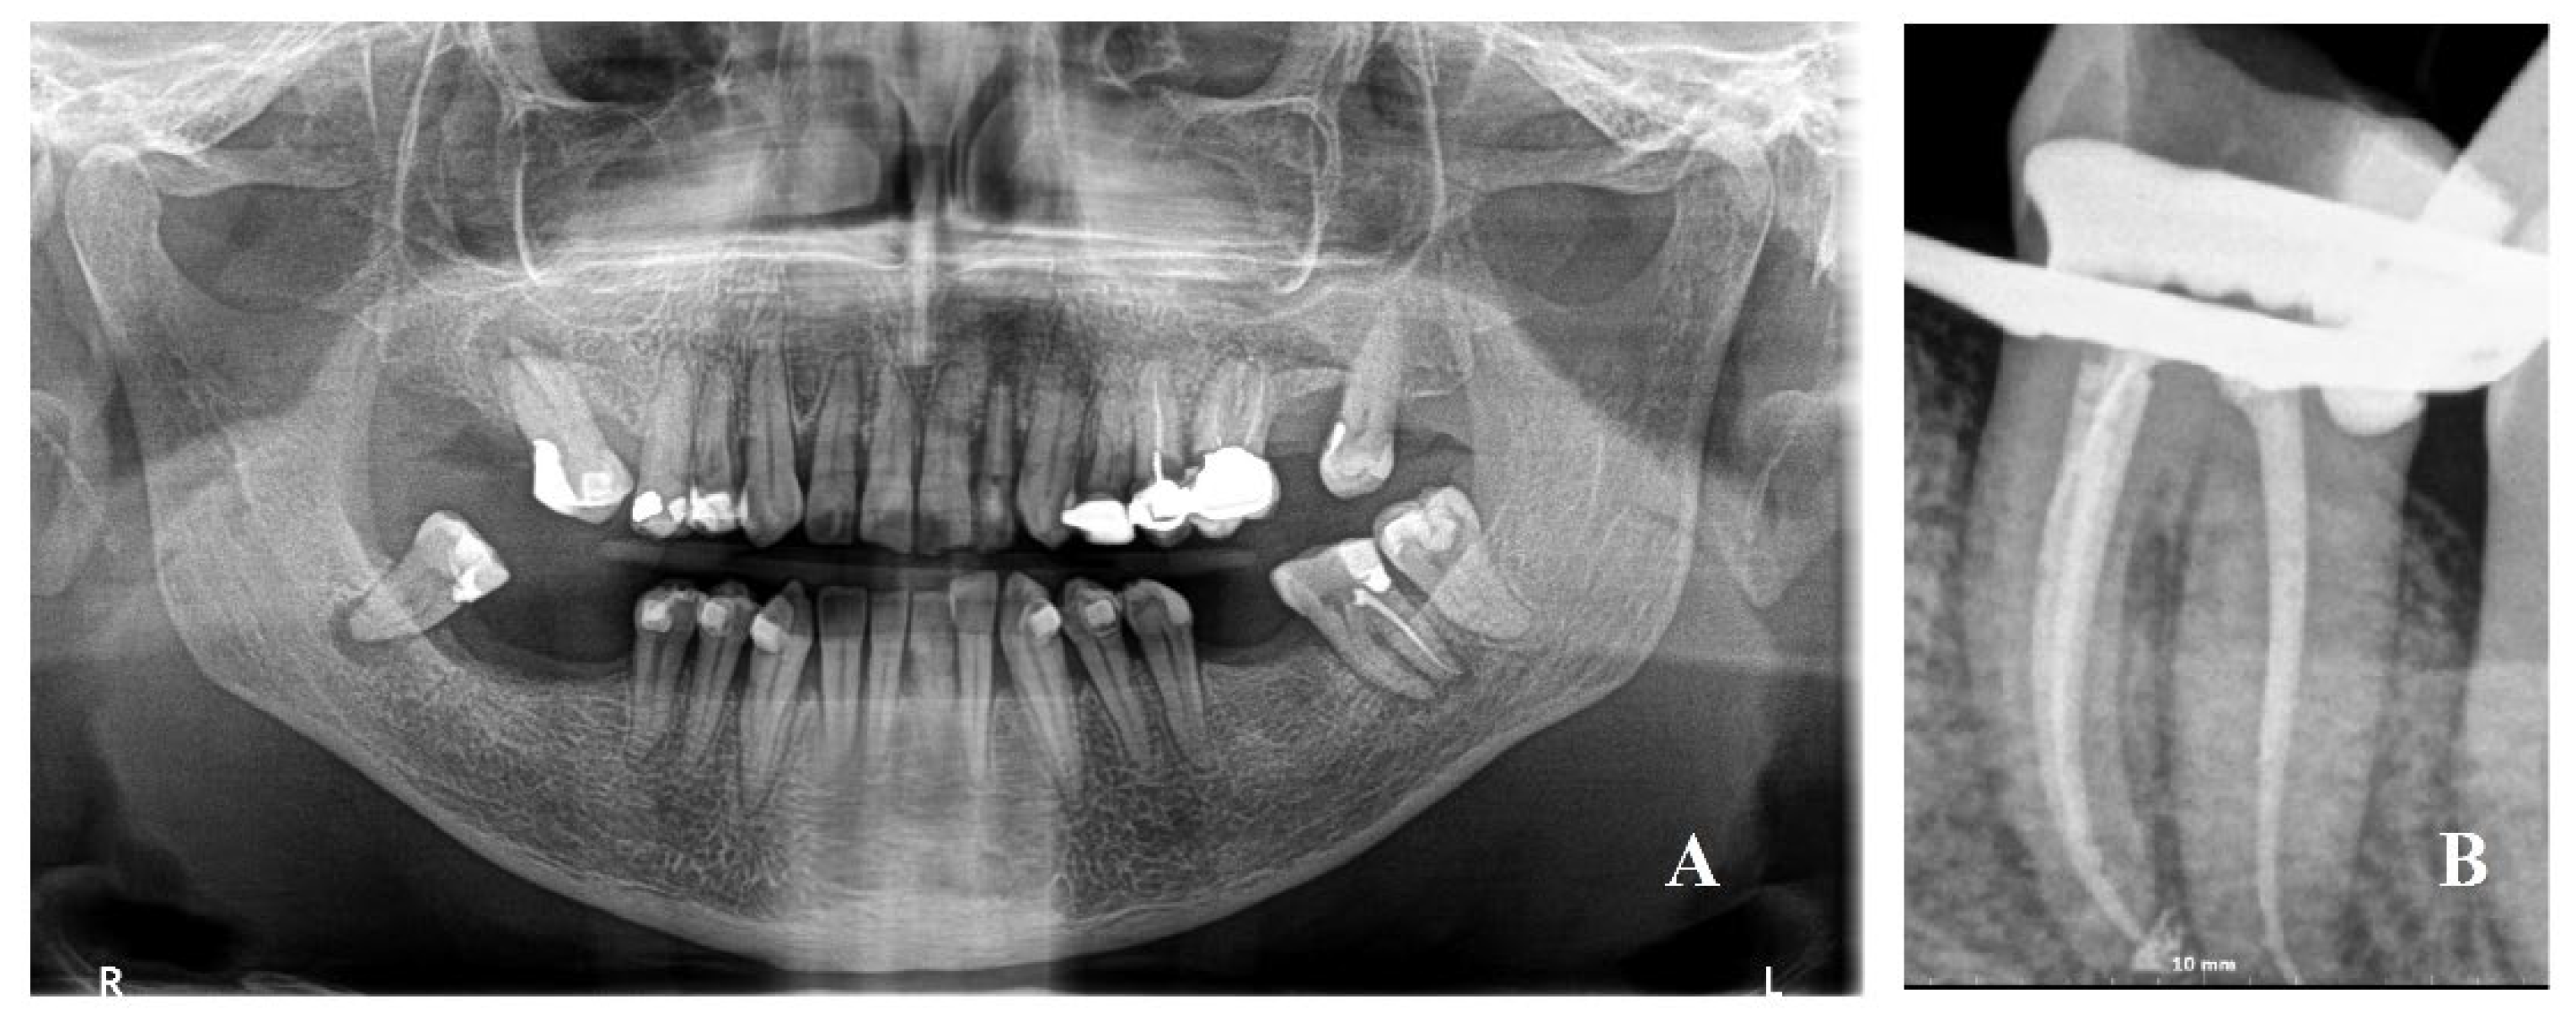

A Caucasian 60-year-old woman (American Society of Anesthesiologists (ASA) I classification) under orthodontic treatment with aligners was referred by her dentist for severe pain on her left second molar in May 2022. She had no history of systemic disease. The patient presented an acute onset of pain that increased with chewing. On the panoramic X-ray, an apical radiolucency to the second molar tooth was identified, along with an incomplete previous root canal treatment. A periapical lesion was identified as responsible for the severe pain of the emergency visit. The emergency treatment provided ibuprofen 600 mg 1× every 12 h until pain decreased and amoxicilline 875 + 125 mg every 12 h each day for 6 days to avoid chewing with the left side; lower aligners were modified on the left second molar. Endodontic retreatment was scheduled 10 days after the visit (Figure 1).

Figure 1. (A) Panoramic X-ray with a periapical lesion of the left mandibular second molar with mandibular foramen very posterior; (B) periapical X-ray after the endodontic retreatment.